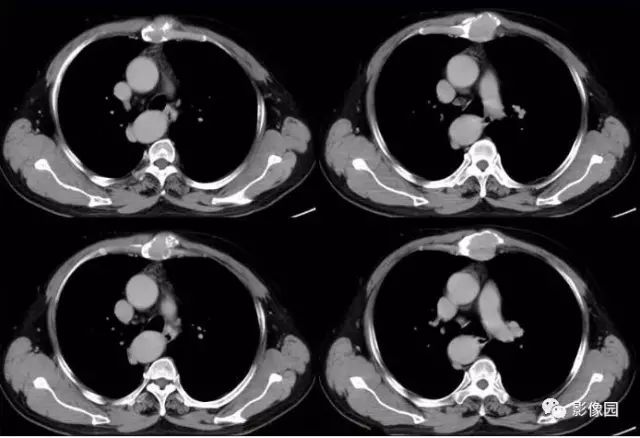

肚肚丫头: 胸骨体局部呈膨胀性骨质吸收破坏,内呈软组织密度影,可见点状钙化,增强扫描呈轻度强化,周围软组织略肿胀。考虑:1.骨巨细胞瘤;2.浆细胞瘤;3.嗜酸性肉芽肿

CT表现:特征性穿凿状、鼠咬状及蜂窝状骨破坏,边缘清楚,骨质疏松,病理性骨折及软组织肿块等表现,骨质硬化及骨膜反应少见。

骨破坏区完全为软组织取代,骨质膨胀,边界清楚,常突破骨皮质形成软组织肿块。增强扫描可见病灶轻中度强化,一般于静脉期达峰值。